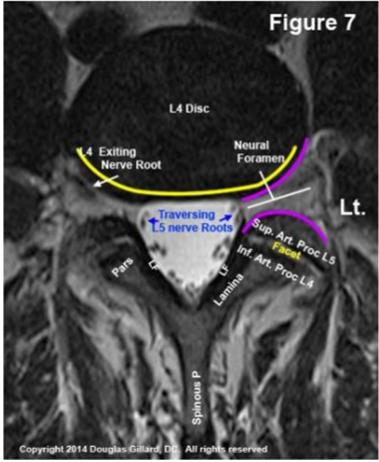

Đặc điểm giải phẫu quan trọng ở bệnh lý đĩa đệm thắt lưng (hình 4):

- Ở vùng thắt lưng, rễ thần kinh thoát ra bên dưới và sát với chân cung của đốt sống cùng tên

- Khoảng gian đốt sống nằm dưới chân cung

- Không phải tất cả các bệnh nhân có 5 đốt sống thắt lưng

Hình 4. Các kiểu thoát vị đĩa đệm và sự chèn ép rễ thần kinh (nguồn: operativeneurosurgery.com)